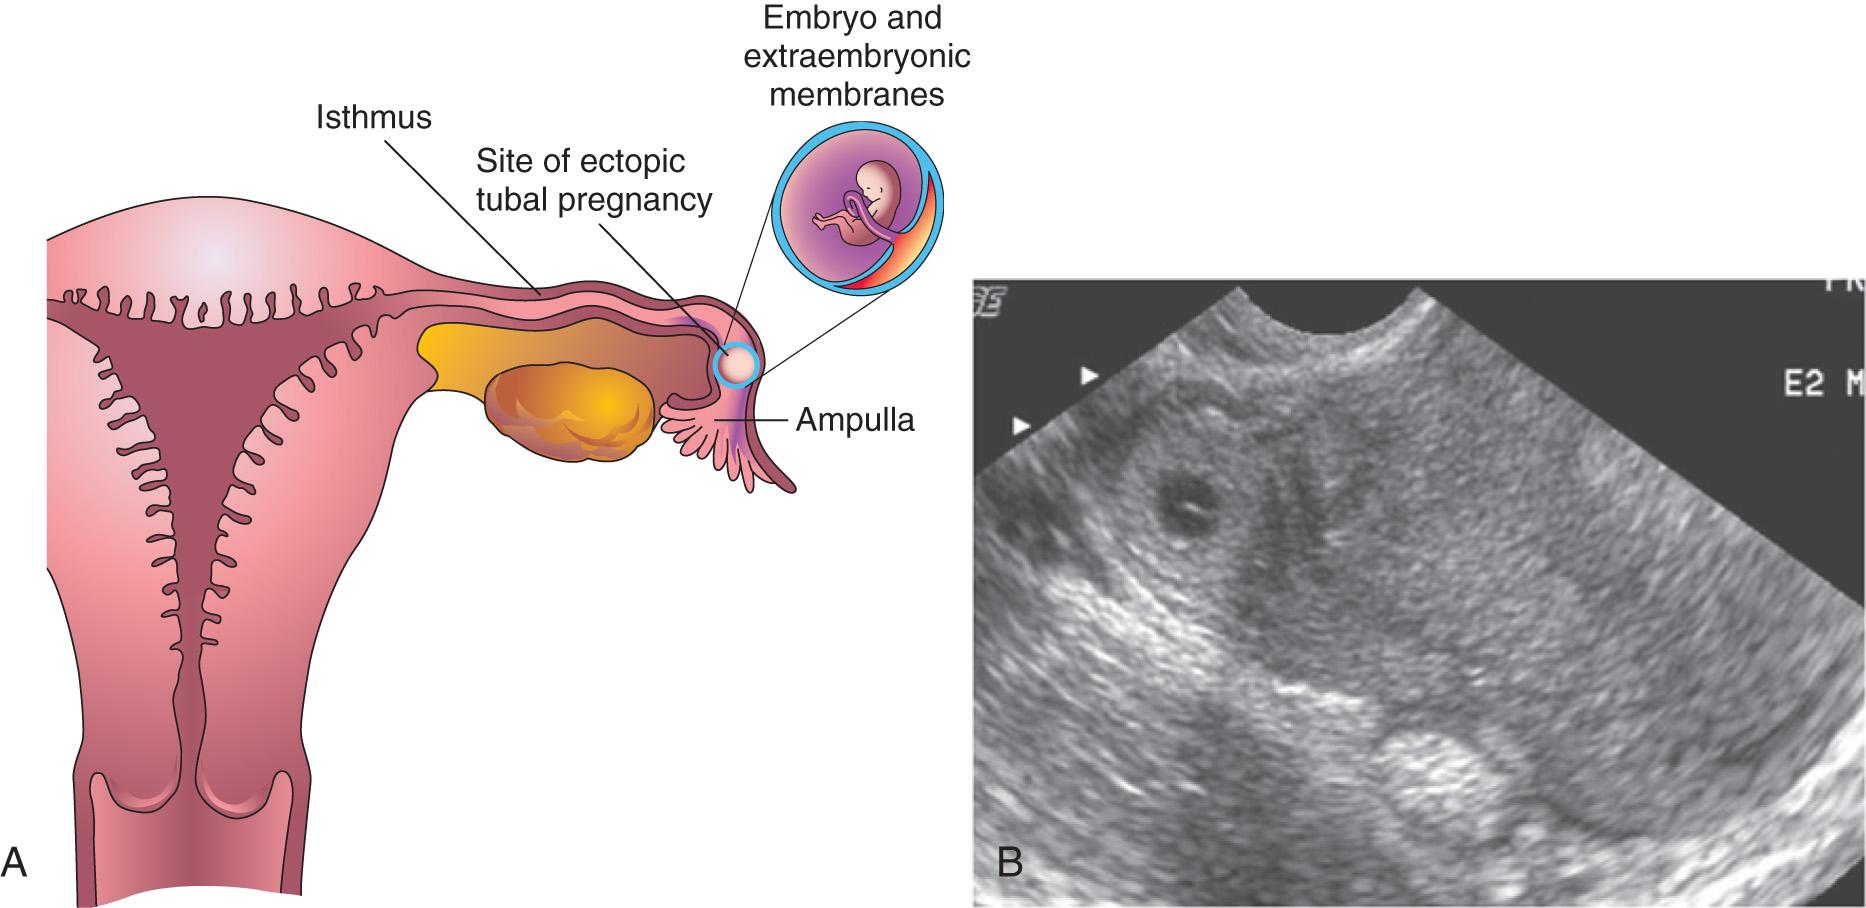

Blastocysts sometimes implant outside the uterus (ectopic sites). These implantations result in ectopic pregnancies ; 95% to 98% of ectopic implantations occur in the uterine tubes, most often in the ampulla and isthmus ( Figs. 3.8, 3.9, and 3.10 , and see Chapter 2 , Fig. 2.6 B ). The incidence of ectopic pregnancy has increased in most countries, ranging from 1 in 80 to 1 in 250 pregnancies, depending partly on the socioeconomic level of the population. In the United States, the frequency of ectopic pregnancy is approximately 2% of all pregnancies; tubal pregnancy is responsible for about 9% of pregnancy-related deaths.

A woman with a tubal pregnancy has signs and symptoms of pregnancy. She may also experience abdominal pain and tenderness because of distention of the uterine tube, abnormal bleeding, and irritation of the pelvic peritoneum (peritonitis) . The pain may be confused with appendicitis if the pregnancy is in the right uterine tube. Ectopic pregnancies produce β-human chorionic gonadotropin at a slower rate than normal pregnancies; consequently, β-human chorionic gonadotropin assays may give false-negative results if performed too early. Transvaginal ultrasonography is very helpful in the early detection of ectopic tubal pregnancies (see Fig. 3.8 ).

There are several causes of tubal pregnancy, and they are often related to factors that delay or prevent transport of the cleaving zygote into the uterus, for example, by mucosal adhesions in the uterine tube or from blockage of the tube, which is caused by scarring resulting from pelvic inflammatory disease . Ectopic tubal pregnancies usually result in rupture of the uterine tube and hemorrhage into the peritoneal cavity during the first 8 weeks, followed by death of the embryo. Tubal rupture and hemorrhage constitute a threat to the mother's life . The affected tube and conceptus are usually surgically removed (see Fig. 3.10 ). In some situations (with no embryo heartbeat and an embryo diameter of less than 3 cm), one or two oral doses of methotrexate can be used effectively.

Fig. 3.8, A , Frontal section of the uterus and left uterine tube, illustrating an ectopic pregnancy in the ampulla of the tube. B , Ectopic tubal pregnancy. Endovaginal axial sonogram of the uterine fundus and isthmic portion of the right uterine tube. The dark ring-like mass is a 4-week ectopic chorionic sac in the tube.